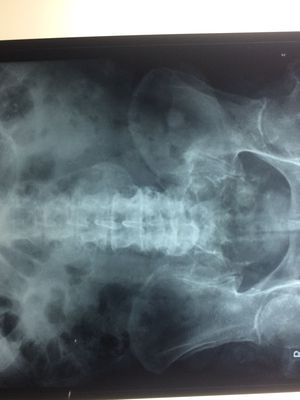

Diagnosis??

Cystic right kidney